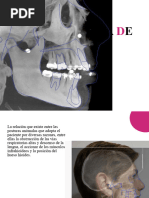

 PERMITIR DESOCLUSION DE LOS DIENTES

POSTERIORES, DEBIDO A LA

SOBREMORDIDA VERTICAL QUE SE HA

PROVEIDO EN LA GUARDA, TAL COMO SE

ENCUENTRA EN UNA OCLUSION

ORGANICA.

 LA FIGURA MOSTRARA EL MOV.

PROTRUSIVO.

 ESTA ES LA SEGUNDA META.